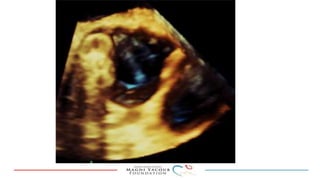

This document provides an overview of percutaneous prosthetic valve leakage (PVL) closure, including indications, approaches, techniques, and closure devices. It discusses that over 210,000 prosthetic valve surgeries are performed each year, with PVL occurring in some cases. While surgical closure has a high mortality rate, percutaneous closure has a procedural success rate of 86% and less complications. Indications for closure include symptomatic heart failure, hemolysis, rocking prosthesis, or leaks over 30% of the sewing ring. Techniques discussed include retrograde and transapical approaches using devices like the Amplatzer and Occlutech plugs. A team approach and techniques like sequential deployment are emphasized for